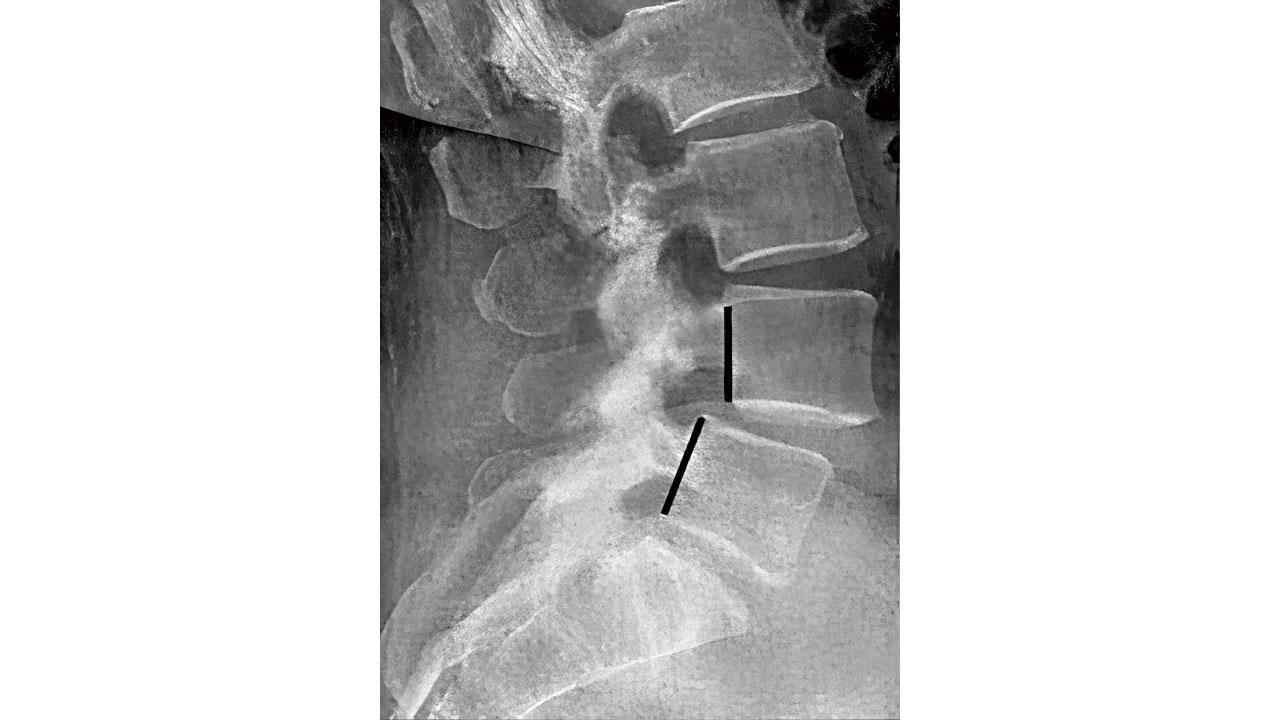

退化性脊椎滑移症的起因,是長期椎節間不穩定形成的脊椎滑移,脊椎面的關節退化及不穩定的移位;滑脫較嚴重的患者可能會出現腰部凹陷,出現台階、腹部前凸,甚至軀幹縮短;走路時出現搖擺,甚至間歇性跛行,一般平躺或休息後疼痛或麻木可以好轉。常規X光檢查可見腰椎椎體向前滑脫,側面X光片可見椎弓根斷裂,與腰椎間盤突出通常不難分辨。